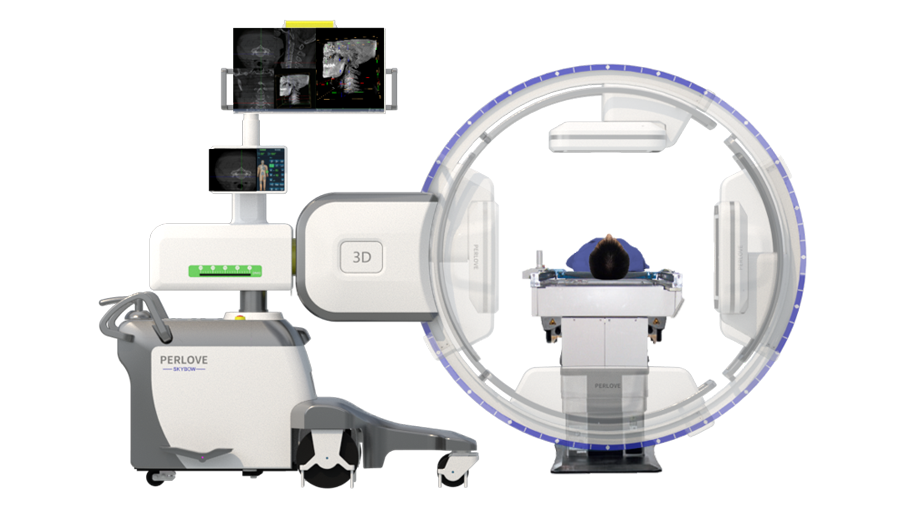

开创三维影像“新视界” PLX C7500A

成像清晰、操作简易、摆位便捷,主要适用于骨科、脊柱外科、矫形外科、创伤骨科及手术室等,能大幅度提升手术水准,降低手术风险和并发症的概率。

术中三维成像和橫断面图像提供多角度的手术诊断信息,辅助医生进行术中评估判断,诸如骨折复位情况和内植入螺钉的尺寸和位置,辅助手术更好地完成。

提供更大的术中三维成像视野,采集更多图像信息,可一次拍全全段颈椎、全段腰椎、七节胸椎、双侧骶髂关节、股骨头及单侧盆骨。